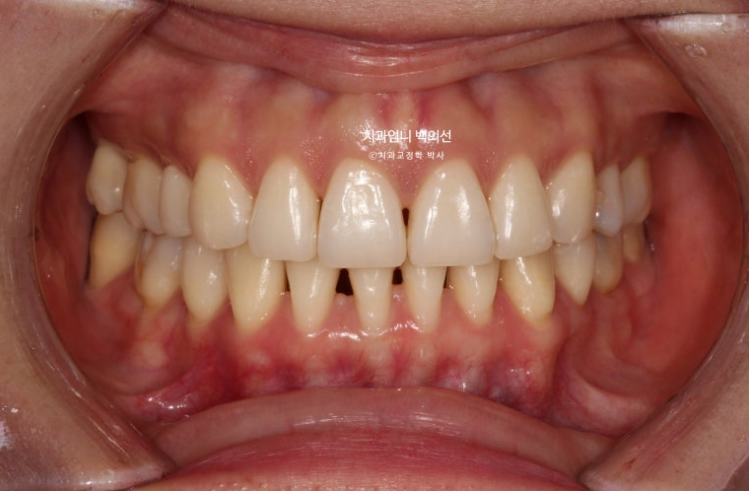

23년 8월 재교정치료를 위해 내원한 환자분입니다.

환자분은 어금니가 닿도록 끝까지 물면 아래턱이 뒤로 밀리는 증상때문에 재교정을 원했습니다.

또한 아래턱이 뒤로 밀리다보니 아래 앞니가 뒤로 너무 쑥 들어가보이는 부분도 개선을 원하셨습니다.

블랙트라이앵글과 중심선 불일치가 보입니다.

잇몸이 얇은편이라 작은어금니 부분에 잇몸퇴축도 보입니다.

얼굴에 비해서 위 앞니 중심선이 좌측으로 돌아간 상태인데

원인은 좌우 치아 갯수 차이에 있었습니다.

오래 전 했던 발치교정으로 작은어금니 4개가 없는 상태인데 좌측 첫번째 큰어금니 1개가 추가로 더 없습니다.

상악 좌측에만 치아갯수가 2개나 없는 것 입니다.